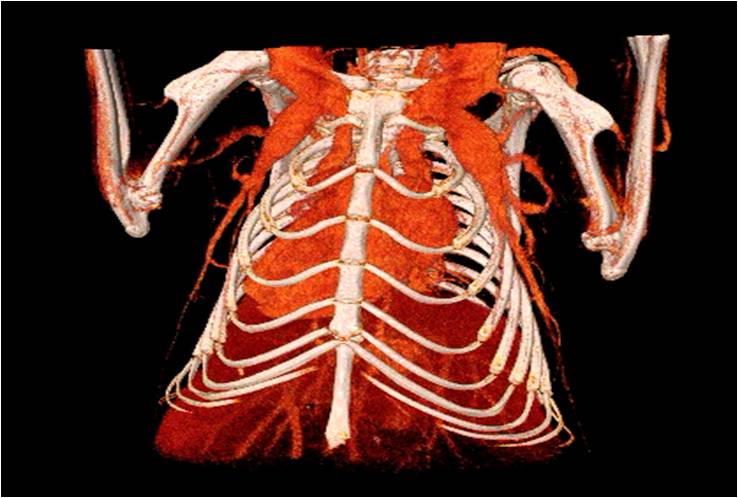

心血管

胸部和心血管的層析成像 胸部和心血管的3D圖像